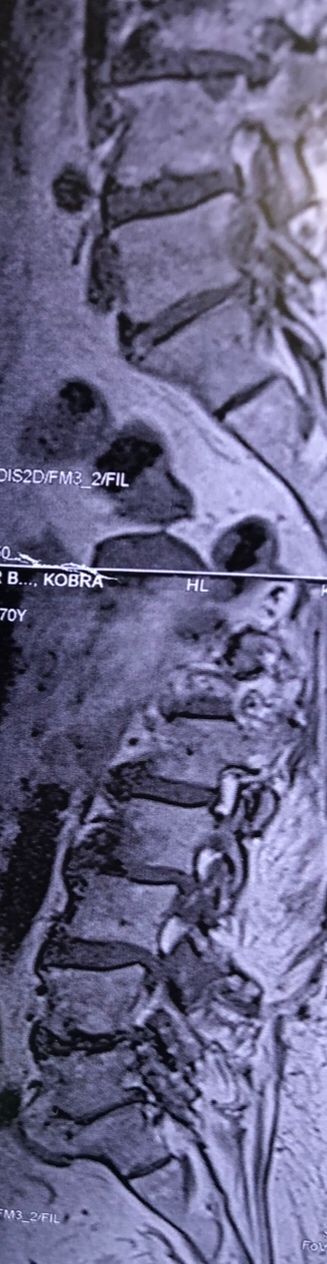

In cervical mri I marked some findings plus their reports

L4-L5 level:

sever L4-5 canal stenosis mainly due to FL hypertrophy?

CSF block. Mild L3 retrolisthesis, facets hypertrophy bilateraly causing L and R IVF stenosis, disc hyperbule

Since I’ve noticed instability in some segments I asked for dynamic L/S x ray:we see mild L4 ant listens due to DjD/DDD. There is not any pars defect.

I will give her treatment via Cox chiropractic flex dis and axial decompression. I would use DTS decompression

Since there is a few mild to moderate DjDs/ DDs in her lower back I won’t use lumbar adjustment on her